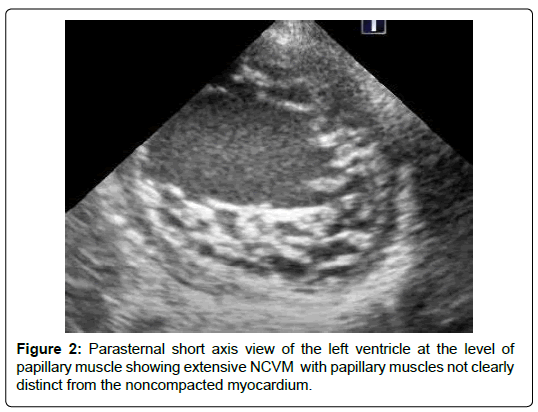

The age ranged between 2 months and 12 years. Females were 66%. Clinical presentations include heart failure in 8 patients (66%), and a heart murmur without symptoms in 4 patients (33%). Echo features in all patients showed NCCM involving PM base. The PM base was discontinuous with the endocardium in 5 patients (41%) (Figures 1). The PM were not well differentiated from the noncompacted myocardium in 3 patients (25%) (Figure 2) There were variable degrees of chordal elongation /rupture. The mitral leaflets appear malcoapting in all patients (n). The anterior leaflet was more affected leading to variable degrees of superior displacement of the leaflet tip and in one case it was flail. MR was severe in 6 patients (50%), moderate in 5 (41%) and mild in 1 patient. Ejection fraction was normal>55% in all 12 patients. Associated congenital heart disease were found in 5 patients (41%) including Ventricular Septal Defects (VSD) in 4 (2 of them had multiple VSDs) and patent ductus arteriosus in one patient.